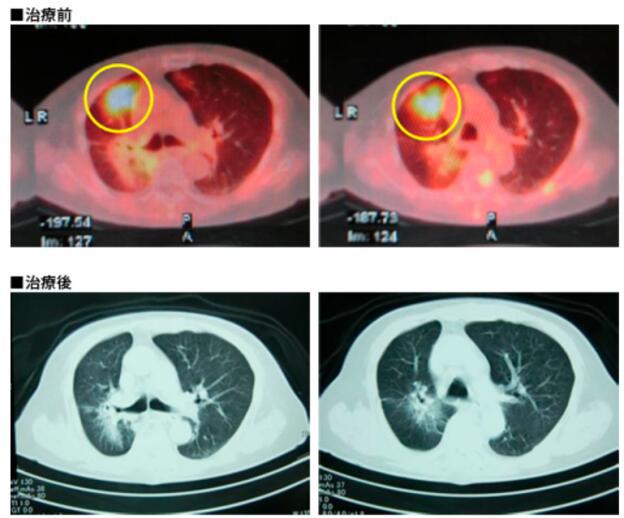

病名:左肺原发转移右肺患者:89岁女性

疗法:树突细胞疫苗+活化NK细胞

经过:左肺原发肺癌,在日本接受放疗后发生放射性肺炎,原发灶消失。但右肺发生转移伴呼吸困难。因

为高龄,只接受了没有副作用的免疫细胞治疗。使用6价树突细胞疫苗和活化NK细胞治疗1个疗程,肺

炎治愈,肿瘤阶段性消退。